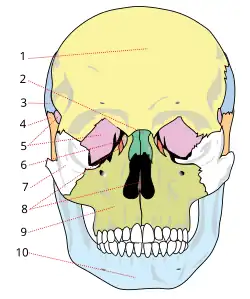

1-Frontais; 6- Lacrimais

2-Nasais; 7-Zigomático

3-Parietais; 8-Etmóide

4-Temporais; 9-Maxila

5-Esfenóide; 10-Mandíbula.

Geralmente, os ferimentos também se apresentam em outras regiões dos ossos faciais como a maxila (o osso que forma a mandíbula superior), a mandíbula (maxilar inferior), e o osso nasal (do nariz). O osso zigomático (osso malar) e o osso frontal (testa) são outros locais de fraturas.[9] As fraturas também ocorrem frequentemente nos ossos do palato e naqueles que se unem para formar a órbita do olho. A mandíbula pode ser fraturada na sua sínfise, corpo, ângulo e ramo.[10]